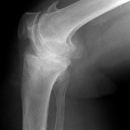

Traumatische Epiphysenlösung

Tibiakopffraktur (nicht disloziert)